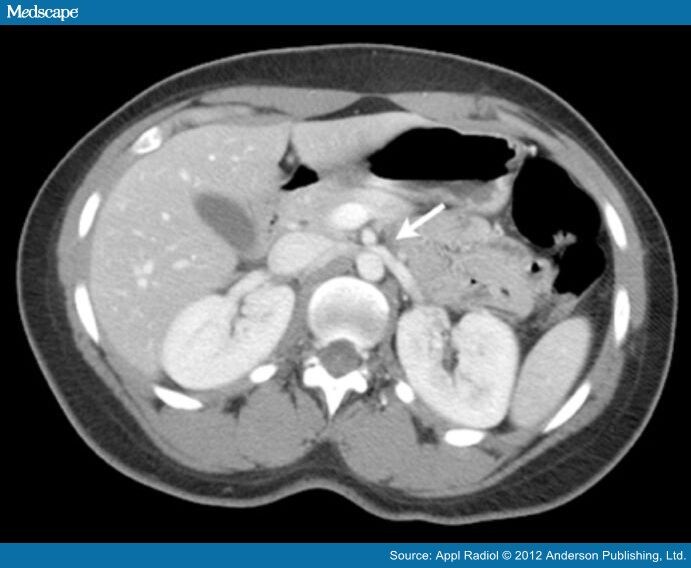

From appliedradiology.com

Posterior Nutcracker Syndrome with Left Renal Vein Duplication Nutcracker Syndrome Medscape Although people with ncs can experience debilitating symptoms, making an accurate diagnosis can often. Nutcracker syndrome (ncs) is an increasingly recognized venous compressive disease. Nutcracker syndrome (ncs) describes left renal vein compression between the superior mesenteric artery and the aorta. Abnormal branching of the superior mesenteric artery from the aorta was identified as the cause of the nutcracker syndrome. Nutcracker. Nutcracker Syndrome Medscape.